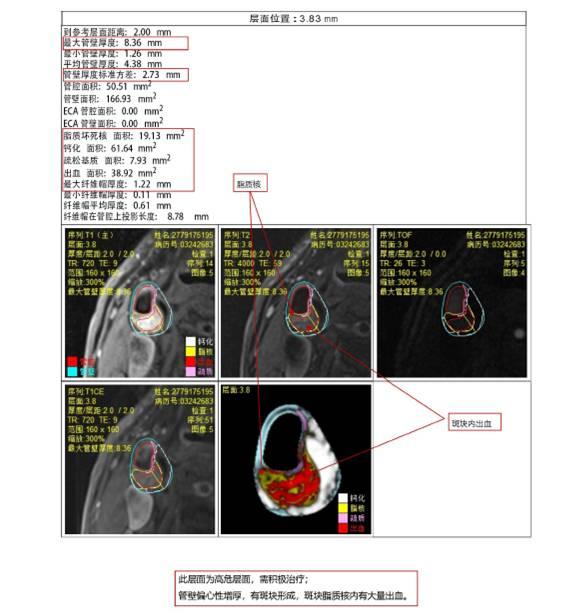

实例说明:

(b)